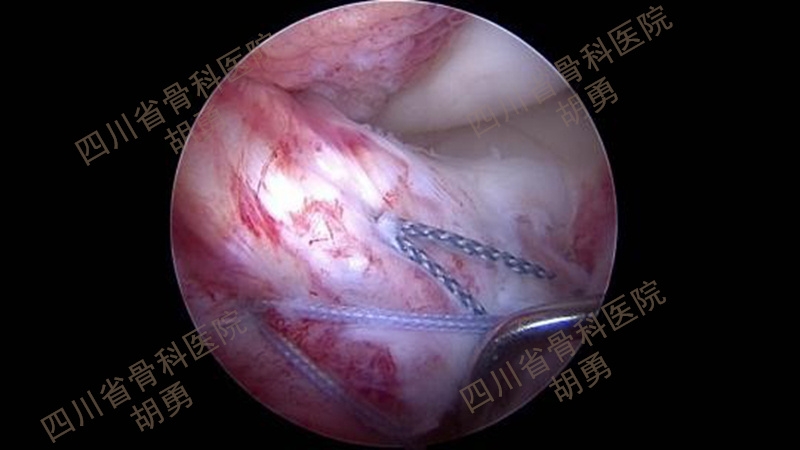

从2016年4月~2020年12月,共计25名4~11岁患儿接受了镜下手术,平均年龄9.2岁。在全部患儿中,有10名病程超过两周,属陈旧性骨折。作者采用了肩袖的镜下缝合桥技术,通过术中透视,所有的操作均在生长板上完成:在骨床后壁胫骨内、外侧髁间嵴连线中点植入一枚内排锚钉,用成角90°半月板全内缝合器将0号PDS线环在前叉韧带后内、后外两侧穿过撕脱骨块,将锚钉自带两种颜色的双骨科高强缝线分别从前叉韧带两侧过线穿过线环,并牵拉穿过撕脱骨块到达骨折表面。再将双色缝线混合引入胫骨骨床提前钻好的两个骨隧道中,双向交叉压迫于撕脱骨块上,调整骨位及缝线位置并拉紧缝线后,完成镜下复位。拉出胫骨隧道后的缝线使用一枚外排钉固定于生长板上。术毕,镜下缝线桥复位及内固定如图1所示,术前及术后MRI如图2和图3所示。术后2~3天,在疼痛缓解的前提下,开始主动康复训练。

图1 缝线桥复位及内固定术后镜下所见

将拉出入口备用的前内及前外骨隧道PDS线环分别引入关节内,使用环钳穿过线环,引入两色骨科高强线各一根,从胫骨隧道拉出线环,将两色缝线各一根混合引入前内及前外骨隧道,如图19所示。调整撕脱骨块骨位及交叉压迫于骨面的缝线位置和牵拉张力后,镜下所见如图1所示。